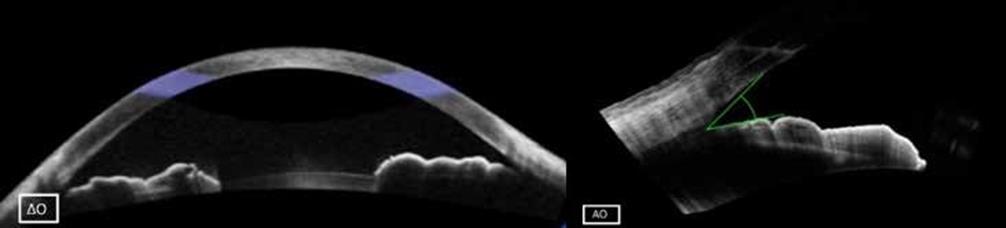

- Στενός πρόσθιος θάλαμος: ΔΑΟ: 0-> I (κατά Shaffer) (Εικόνα 1)

Εικόνα 1.

- Η οπτική τομογραφία συνοχής πρόσθιου ημιμορίου (AS-OCT) έδειξε αύξηση του εύρους της γωνίας (Εικόνα 4)